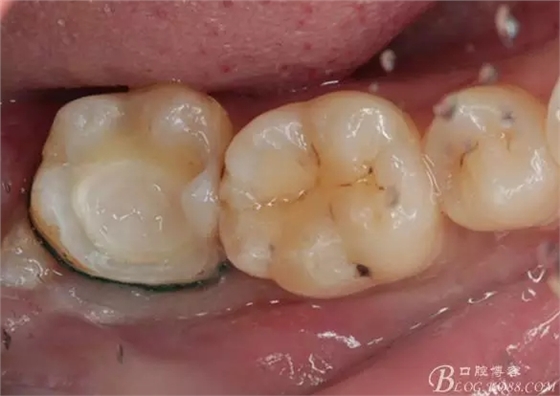

一周后復(fù)診,37臨時充填物完好。去除臨時充填物,清潔基牙,試戴嵌體,就位良好,邊緣密合。取下嵌體,常規(guī)處理,9.5%HF處理20S,沖洗一分鐘,95%酒精蕩洗5分鐘。基牙涂抹37%的磷酸凝膠,釉質(zhì)區(qū)域酸蝕30S,本質(zhì)區(qū)域15S。粘固用的是3M第八代粘接劑套裝,照說明書逐步操作。最終固化時涂滿阻氧劑,每個牙面最少光照30S,光固化燈用漸強模式。常規(guī)調(diào)合,配合硅膠尖套裝拋光。術(shù)后常規(guī)醫(yī)囑,不適隨診。

回訪:術(shù)后一周電話回訪無異常。

④嵌體顏色與基牙的差異也是一遺憾。